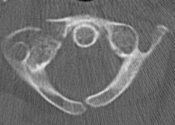

What’s the Diagnosis? Gepost op 9 april 202124 maart 2021 door netwerkvsseh What’s the Diagnosis? By Abby Renko MD @emdaily.cooperhealth.org Dit delen: Delen op X (Opent in een nieuw venster) X Share op Facebook (Opent in een nieuw venster) Facebook Delen op LinkedIn (Opent in een nieuw venster) LinkedIn E-mail een link naar een vriend (Opent in een nieuw venster) E-mail Afdrukken (Opent in een nieuw venster) Print Vind-ik-leuk Aan het laden... Gerelateerd